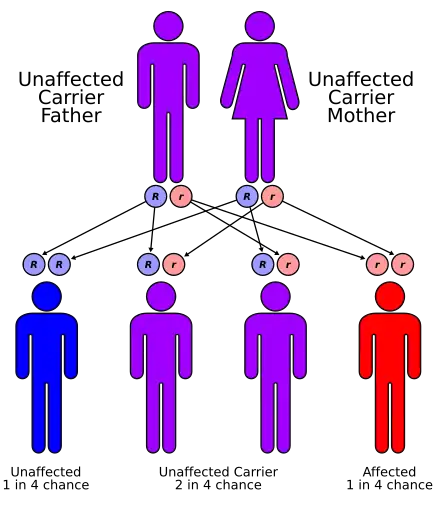

This condition is an autosomal recessive disorder, which means the defective gene is located on an autosome,[6] and two copies of the defective gene are required to inherit the disorder.

Both parents of an individual with an autosomal recessive disorder are carriers of one copy of the gene, but usually do not have the disorder.